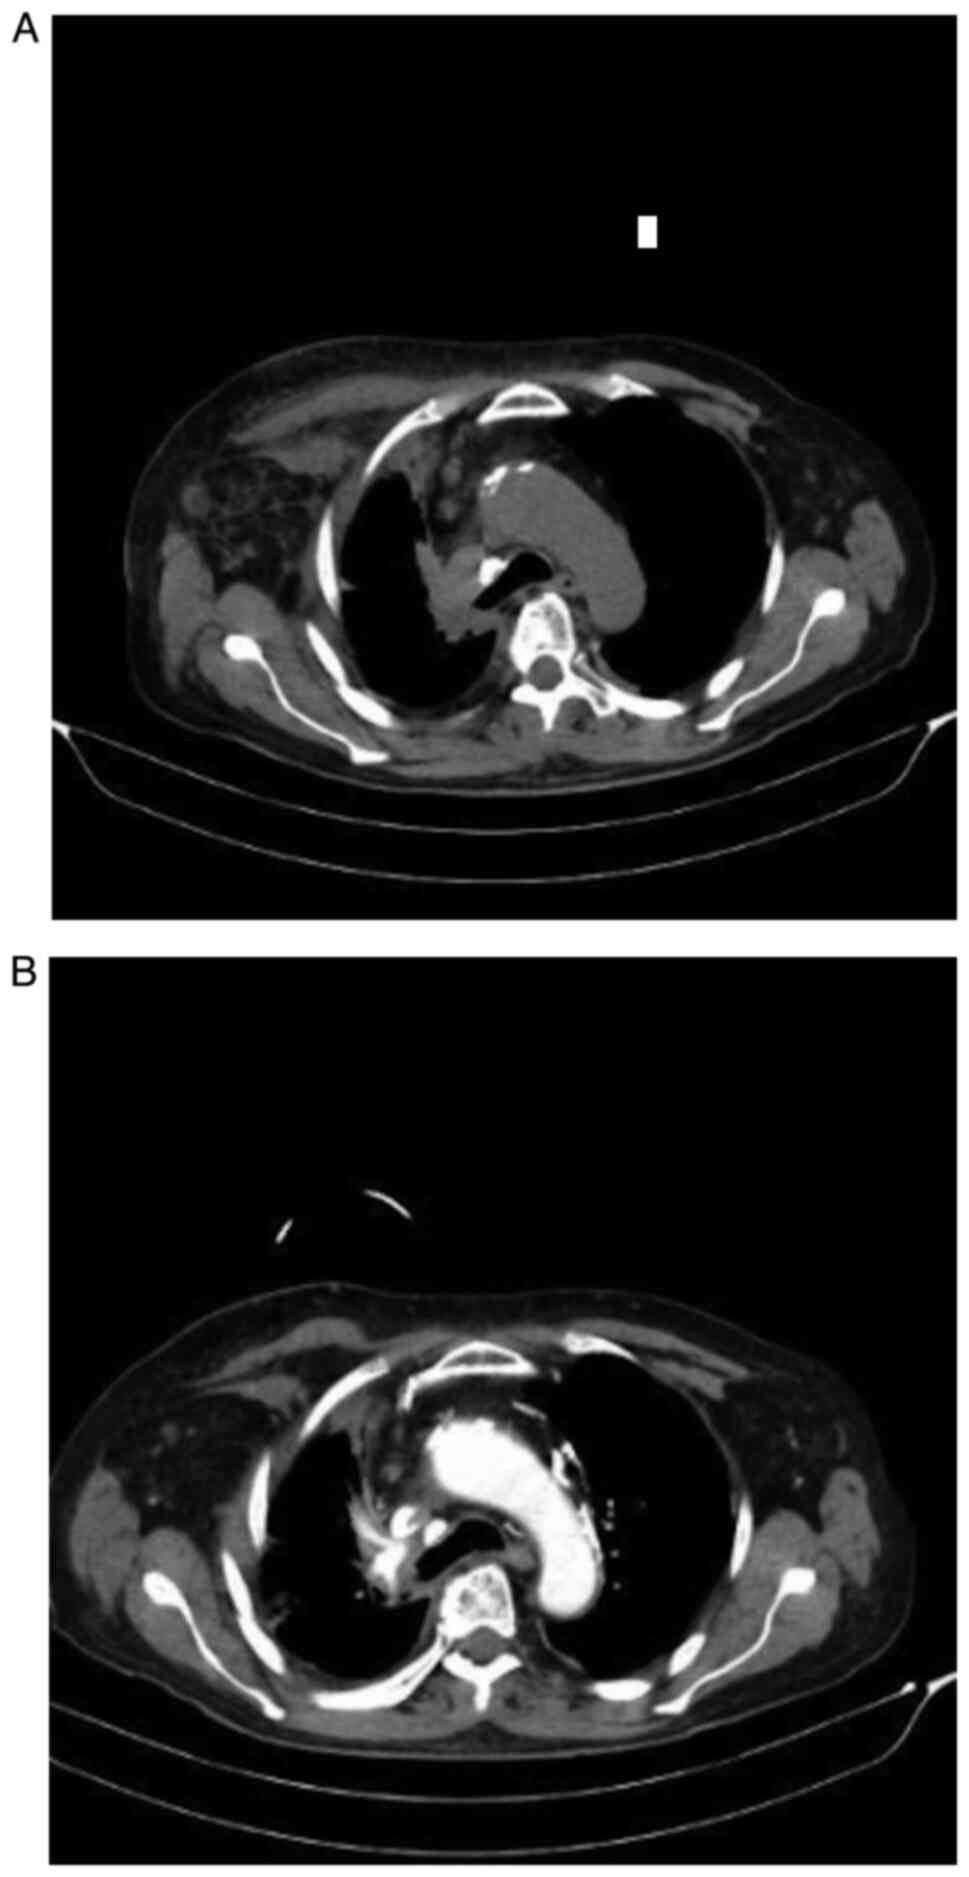

The patient developed a mediastinal compression syndrome (Fig. 4) for which mediastinal radiotherapy was administered with a TD of 30 Gy. Immunotherapy was continued in the subsequent months and was terminated by March 2019, after a thoracic CT scan was carried out which revealed progressive disease (Fig. 5A and B).

Figure 5

(A and B) CT of the thorax. Progressive disease is evident. CT, computerized tomography.